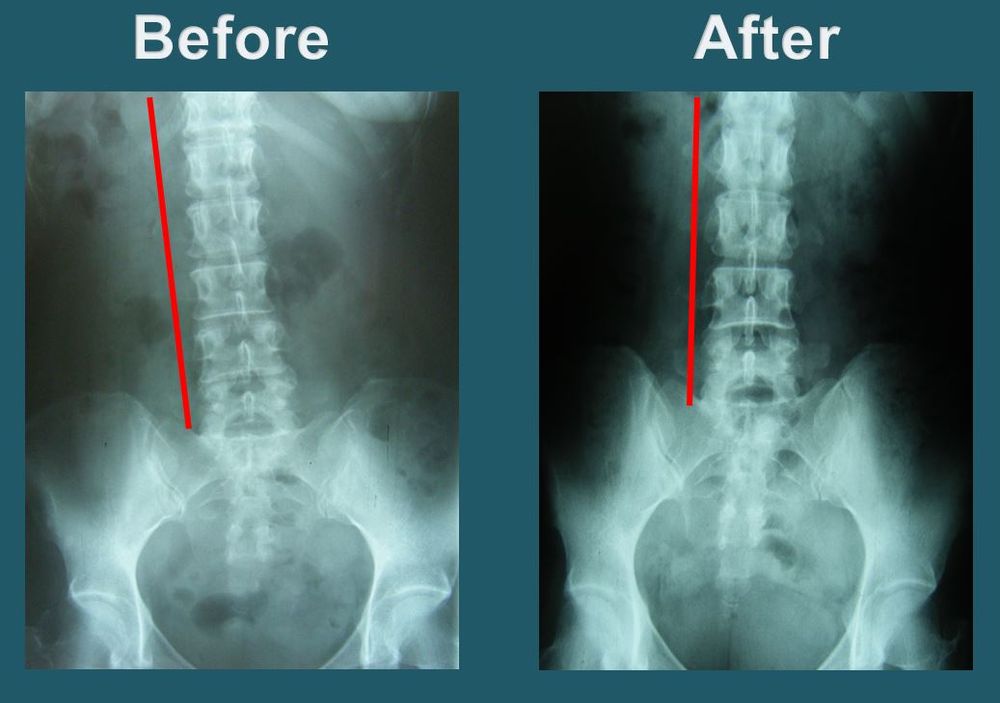

Side-scroll through X-rays captured before and after treatment.